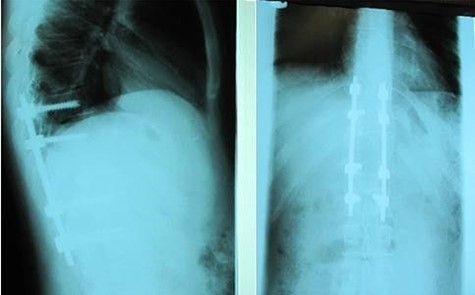

A 24-year-old male presented with acute low back pain with no prior traumatic events. Physical examination was unremarkable except for tenderness over the lower thoracic spine. The laboratory tests including complete blood count, renal function tests, alkaline phosphatase, aspartate aminotransferase, alanine aminotransferase, serum calcium, serum phosphorus and parathyroid hormone were all within normal limits. Initially, the patient was treated conservatively but the pain did not improve. Lumbar X-ray showed mild height loss and fracture of the superior endplate of T12 vertebra (Fig. 1). Computed tomography (CT) showed a multi-lobulated osteolytic lesion within the T12 body with extension to the right pedicle and transverse process (Fig. 2). Magnetic resonance imaging (MRI) revealed a well-defined lesion with low signal intensity on T1 and high signal intensity on T2 weighted images (Fig. 3). The bone scan showed a cold spot at the site of the lesion. The patient underwent surgery and excisional biopsy through the posterior approach. A large clear fluid-filled cavity was curetted and the cavity was filled with an autologous bone graft from iliac crest. Posterior spinal fusion was performed with instrumentation with pedicle screws from T10 to L2 and a mixture of autologous bone graft and allograft was used to achieve better fusion (Fig. 4). Pathology report confirmed the diagnosis of SBC and the patient received no further treatment (Fig. 5). The patient had no recurrence in 10-year follow up.

Case 1, (A): Anterior–posterior; (B): Lateral pre-operative X-ray.